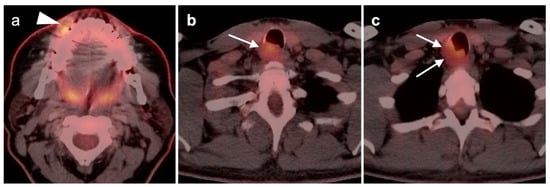

2.6. Thyroid Cancer

- Anaplastic thyroid cancer

- 4.